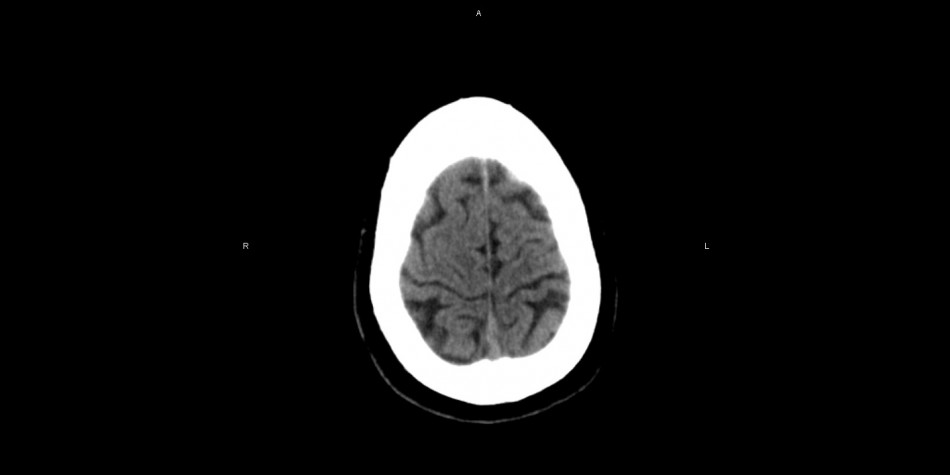

International MRC Group - Departamento de Asuntos Regulatorios - Mayo 24/2022 Tras un acuerdo firmado entre el Departamento de Asuntos Regulatorios de MRC Group en UK, LATAM y US, se ha puesto en marcha un programa de aceleración de los procesos regulatorios en función de una programática diseñada por el CEO Internacional y CEO Regulatorio, Especialista Lic. Maximiliano R.L.B. a cargo de todas las funciones integrales de esta estructura. Considerando las diferentes normas que rigen dentro de CE, US, Países que integran la Red de Habla Inglesa, NHS en UK, y Asociados a los países dentro del Espacio Schengen, Medio Oriente, la India y EAU, se ha establecido este sistema que nos permite garantizarle a nuestras empresas productoras, distribuidoras y a los clientes que consumen todos los productos relacionados con HealthCare y, además, productos farmacéuticos, lograr un mejor encuadre de los marcos regulatorios locales e internacionales a fin de agilizar los procesos frente a la Autoridad Sanitaria facilitándole a esta el acceso a la información. Gracias al Equipo de Tecnología Médica y Radiobiología, Bioequivalencia y Farmacogenómica, dirigido también por el CEO Internacional y Regulatorio de MRC, se han obtenido resultados mucho mas rápidos y mas eficientes en relación a la interacción de la tecnología médica con el cuerpo humano y la respuesta de los fármacos y drogas bioequivalentes. Durante las reuniones precedidas este martes por Maximiliano R.L.B. nos indicó "-(...)es un paso muy importante el que estamos dando y lo hacemos con grandes capitales en la industria que realmente están preocupados por mejorar sus procesos. Agradezco en este punto a toda la experiencia adquirida a lo largo de mi carrera, otros trabajos, además de ser actualmente el CEO, cuando no lo era, cuando crecí en mi campo de acción, tanto desde los rechazos como desde la aceptación, realmente hemos logrado algo que ningún otra empresa ha logrado y es anticiparnos al futuro, hoy podemos determinar desde nuestro equipo regulatorio, en función del trabajo conjunto y multidisciplinario, con mayor eficiencia y eficacia, como va a responder un individuo a la aplicación de magnetismo, radiación, drogas farmacéuticas, etc. Si bien eso como tal no es la gran novedad, el hecho de poder proyectarlo a futuro y haber logrado mas del 98,9% de éxito en las predicciones matemáticas y regulatorias, y obviamente agradeciendo a mi equipo que no obtuvo el apoyo de nadie para hacerlo, ni laboratorios, ni gubernamentales, realmente, hoy demostramos no solo que se puede llegar mucho mas allá en el campo de la inocuidad, la calidad, la eficiencia y el contrarrestado de problemas sintomáticos, sino además le he podido demostrar a mi equipo que no necesitan a nadie, mas allá de ellos mismos. Si le agradezco a los laboratorios internacionales que se nos han acercado hoy, en total han sido 16, y francamente hubiera esperado verlos antes, pero, sea por el bien de todos, al menos estos 16 entendieron lo que era importante". En los próximos días el CEO Internacional espera tener diferentes reuniones con otros laboratorios en función de estas nuevas estructuras que afectan directamente la mejor competencia de los productores en beneficio de la salud de los consumidores. Prensa MRC Group